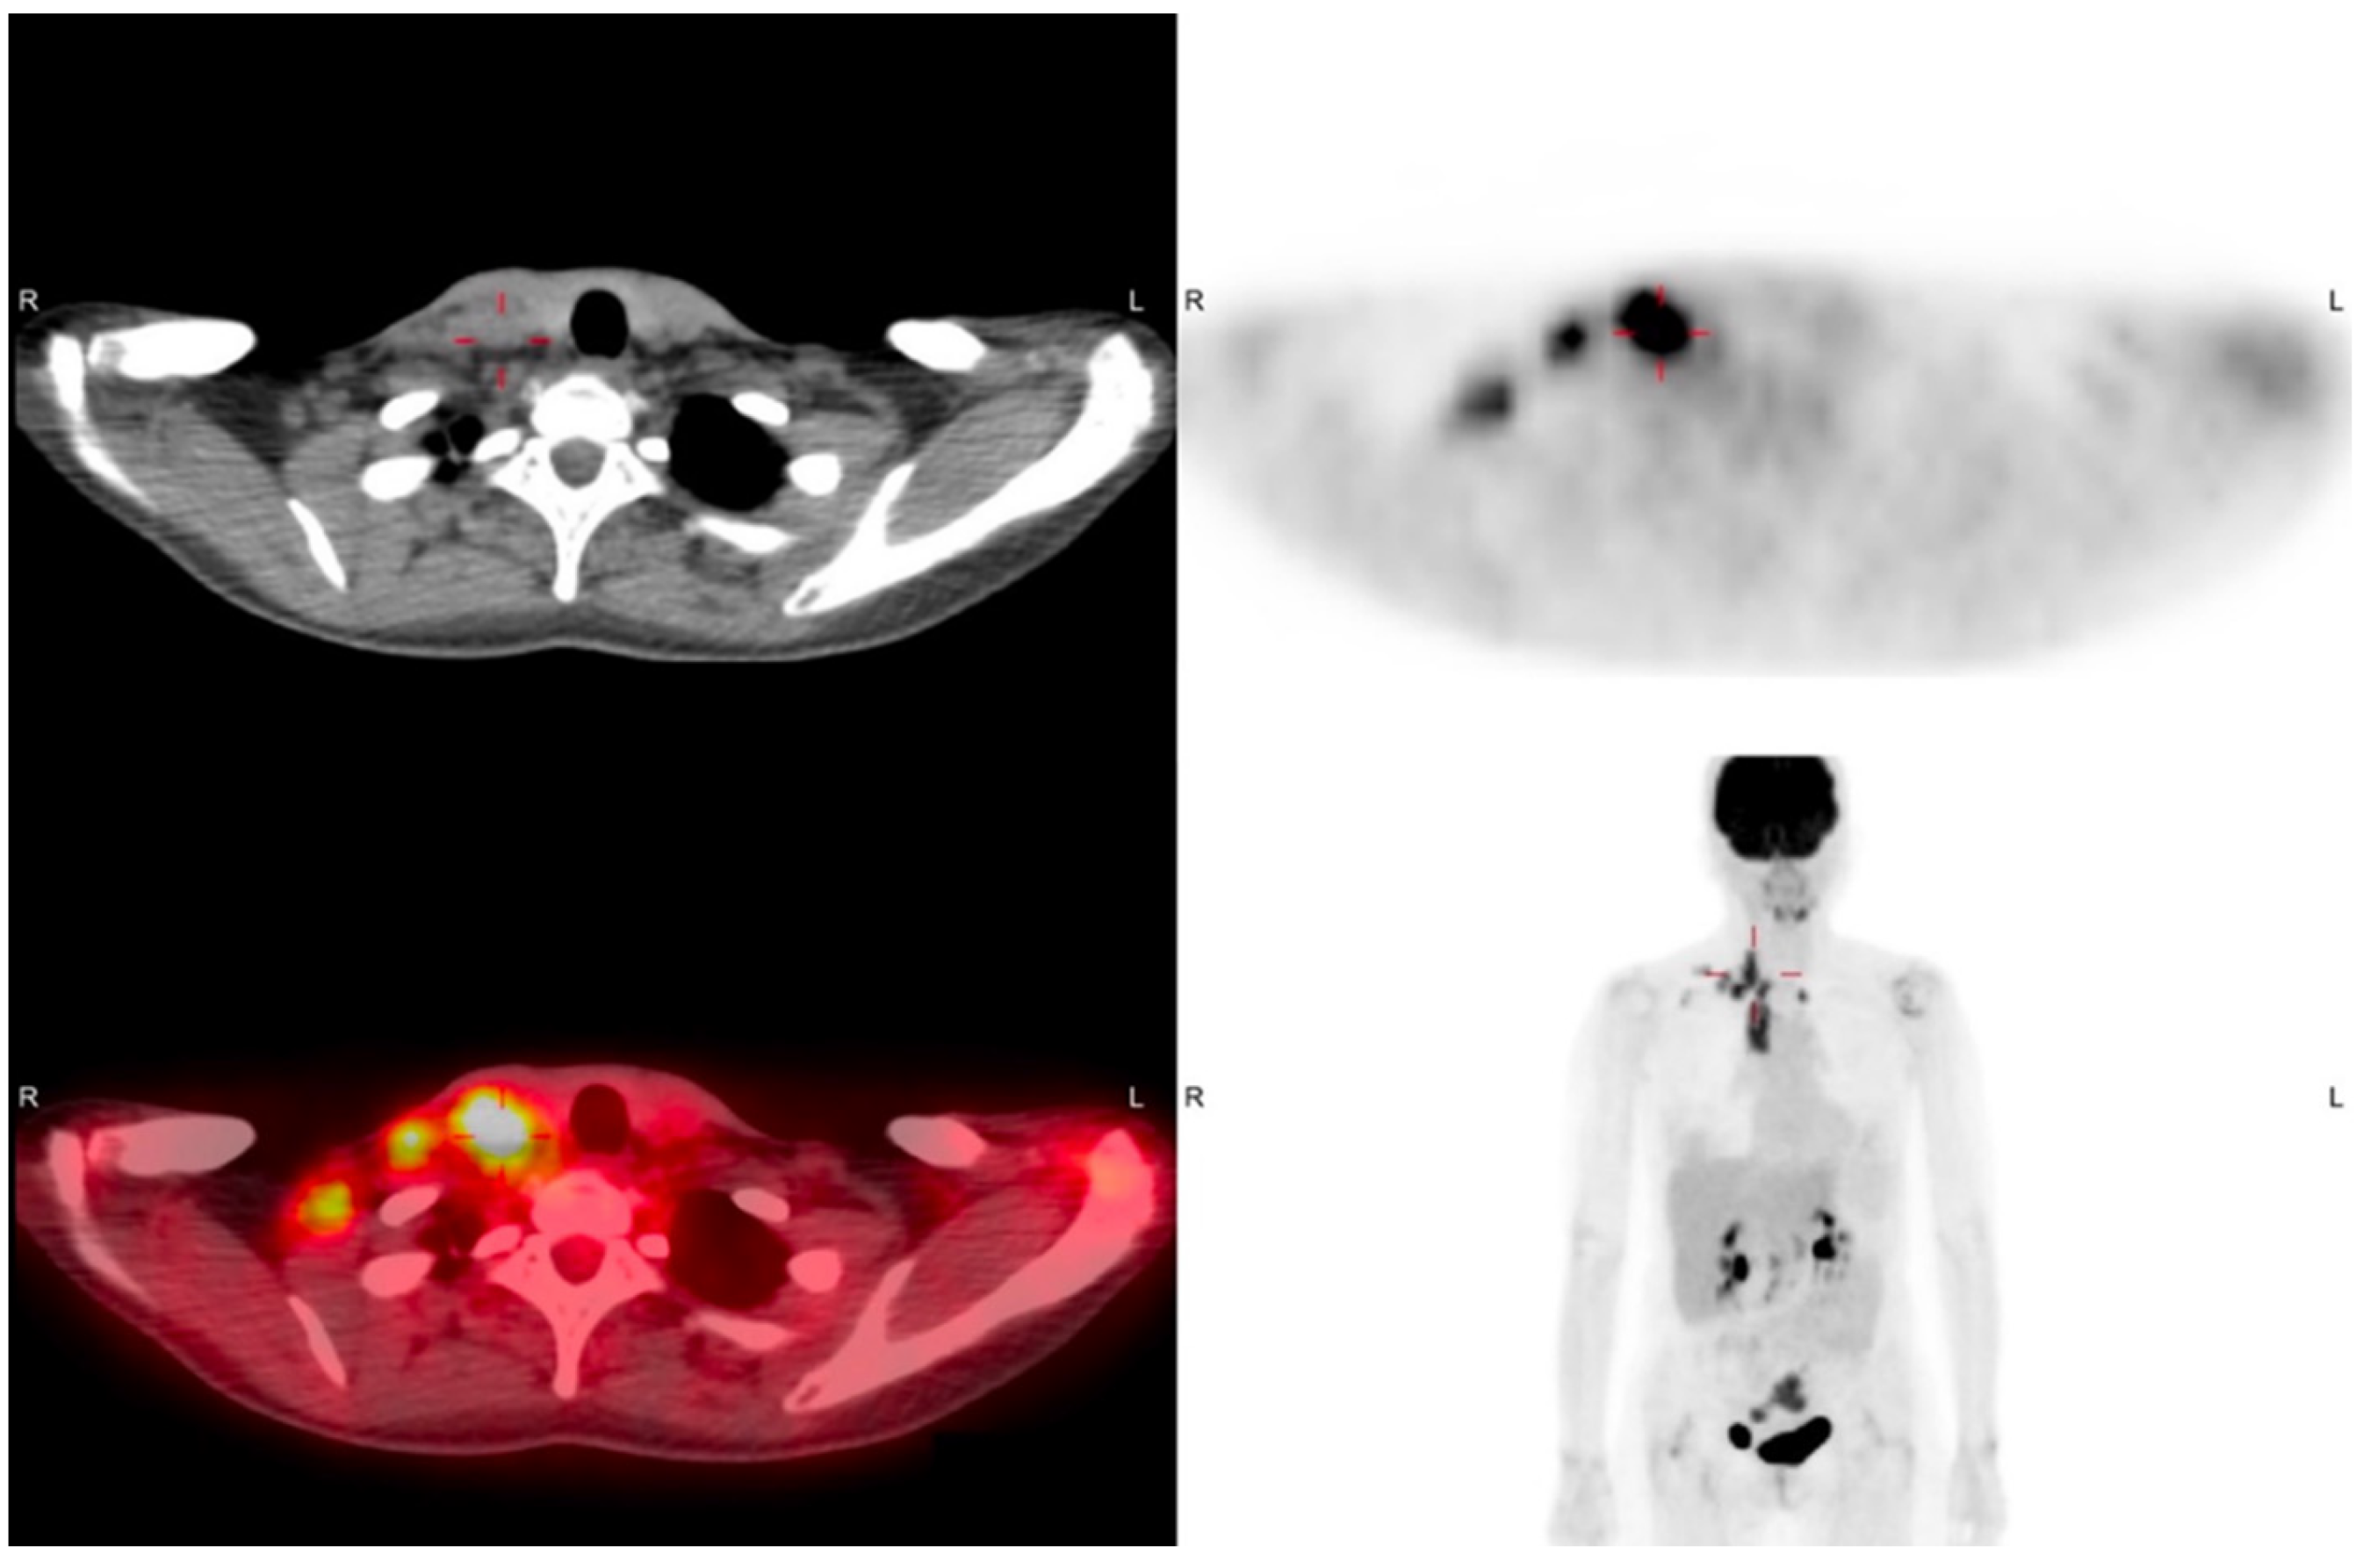

| Present case, 2021 | 53 | US, PET/CT | FNAC, excision | Serous adenocarcinoma | Low-grade | C | AWD, 2 |